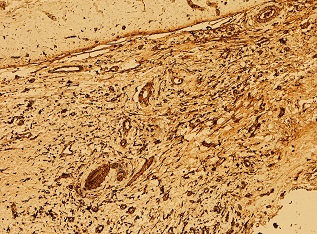

Case description: A 59-year-old Caucasian man presented with transitional episodes of tinnitus and an unspecific headache. Imaging studies (magnetic resonance imaging – MRI) demonstrated a thickened dura mater. Lymphoma was suspected due to an abnormal flow cytometric analysis of a cerebrospinal fluid (CSF) sample. Hematological diagnostics including bone marrow biopsy, whole body computed tomography (CT) and digestion tract examination were performed leading to the exclusion of hematological malignancy. The patient underwent surgery, and a specimen from the lesion was obtained. On this basis, intracranial idiopathic hypertrophic pachymeningitis was diagnosed. First line treatment strategy was introduced with corticosteroids with a gradual dose reduction. After the 48-month follow-up, we observed an alleviation of symptoms with a gradual significant decrease in the thickening of dura matter with almost complete resolution.